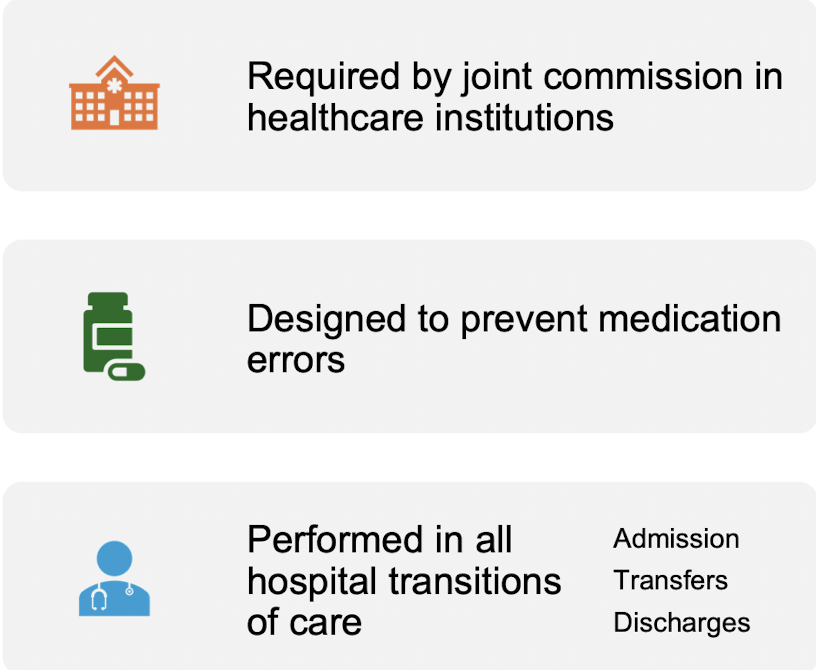

Medication Reconciliation

-review with patient and family the name, dosage, frequency, timing, and duration of all medications patient is taking at home; check allergies and intolerances